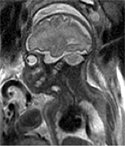

The Baby Brain Research Group studies how newborns' brains get injured and what the best diagnostic tools are to see that injury early on. Our aim is to see brain injury early enough so we can develop treatments to reduce the damage and aid recovery of injured areas. We also hope to identify those children whose long-term development will be affected, and who could benefit from early therapy.